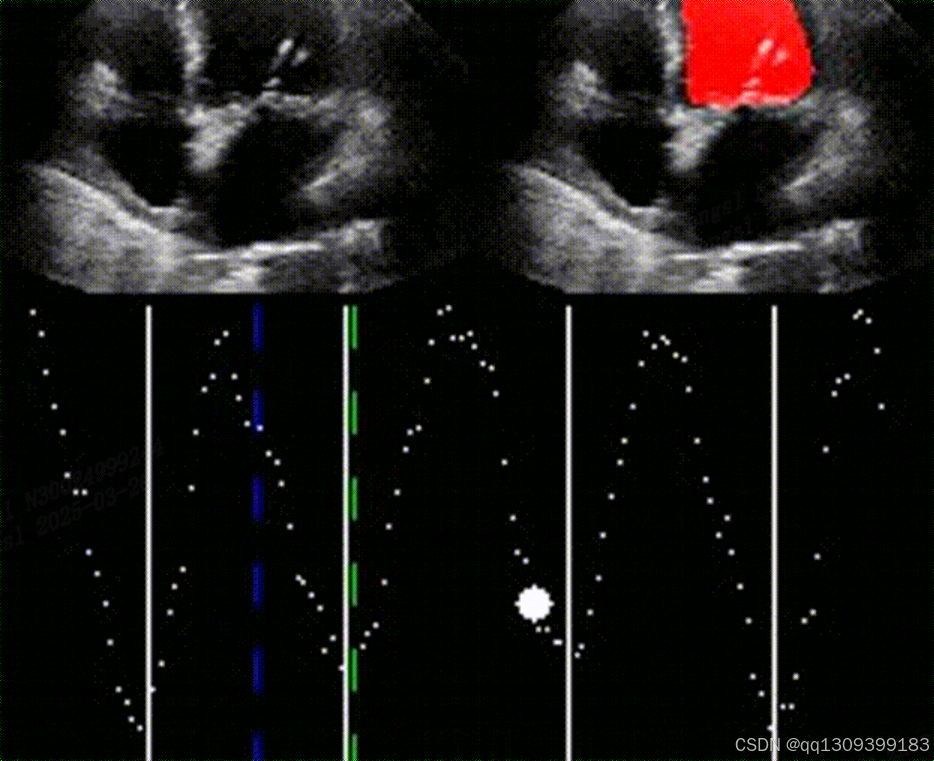

- 可视化验证:分割结果清晰勾勒左心室内膜边界(见图1),且在低信噪比帧中仍保持稳定性。